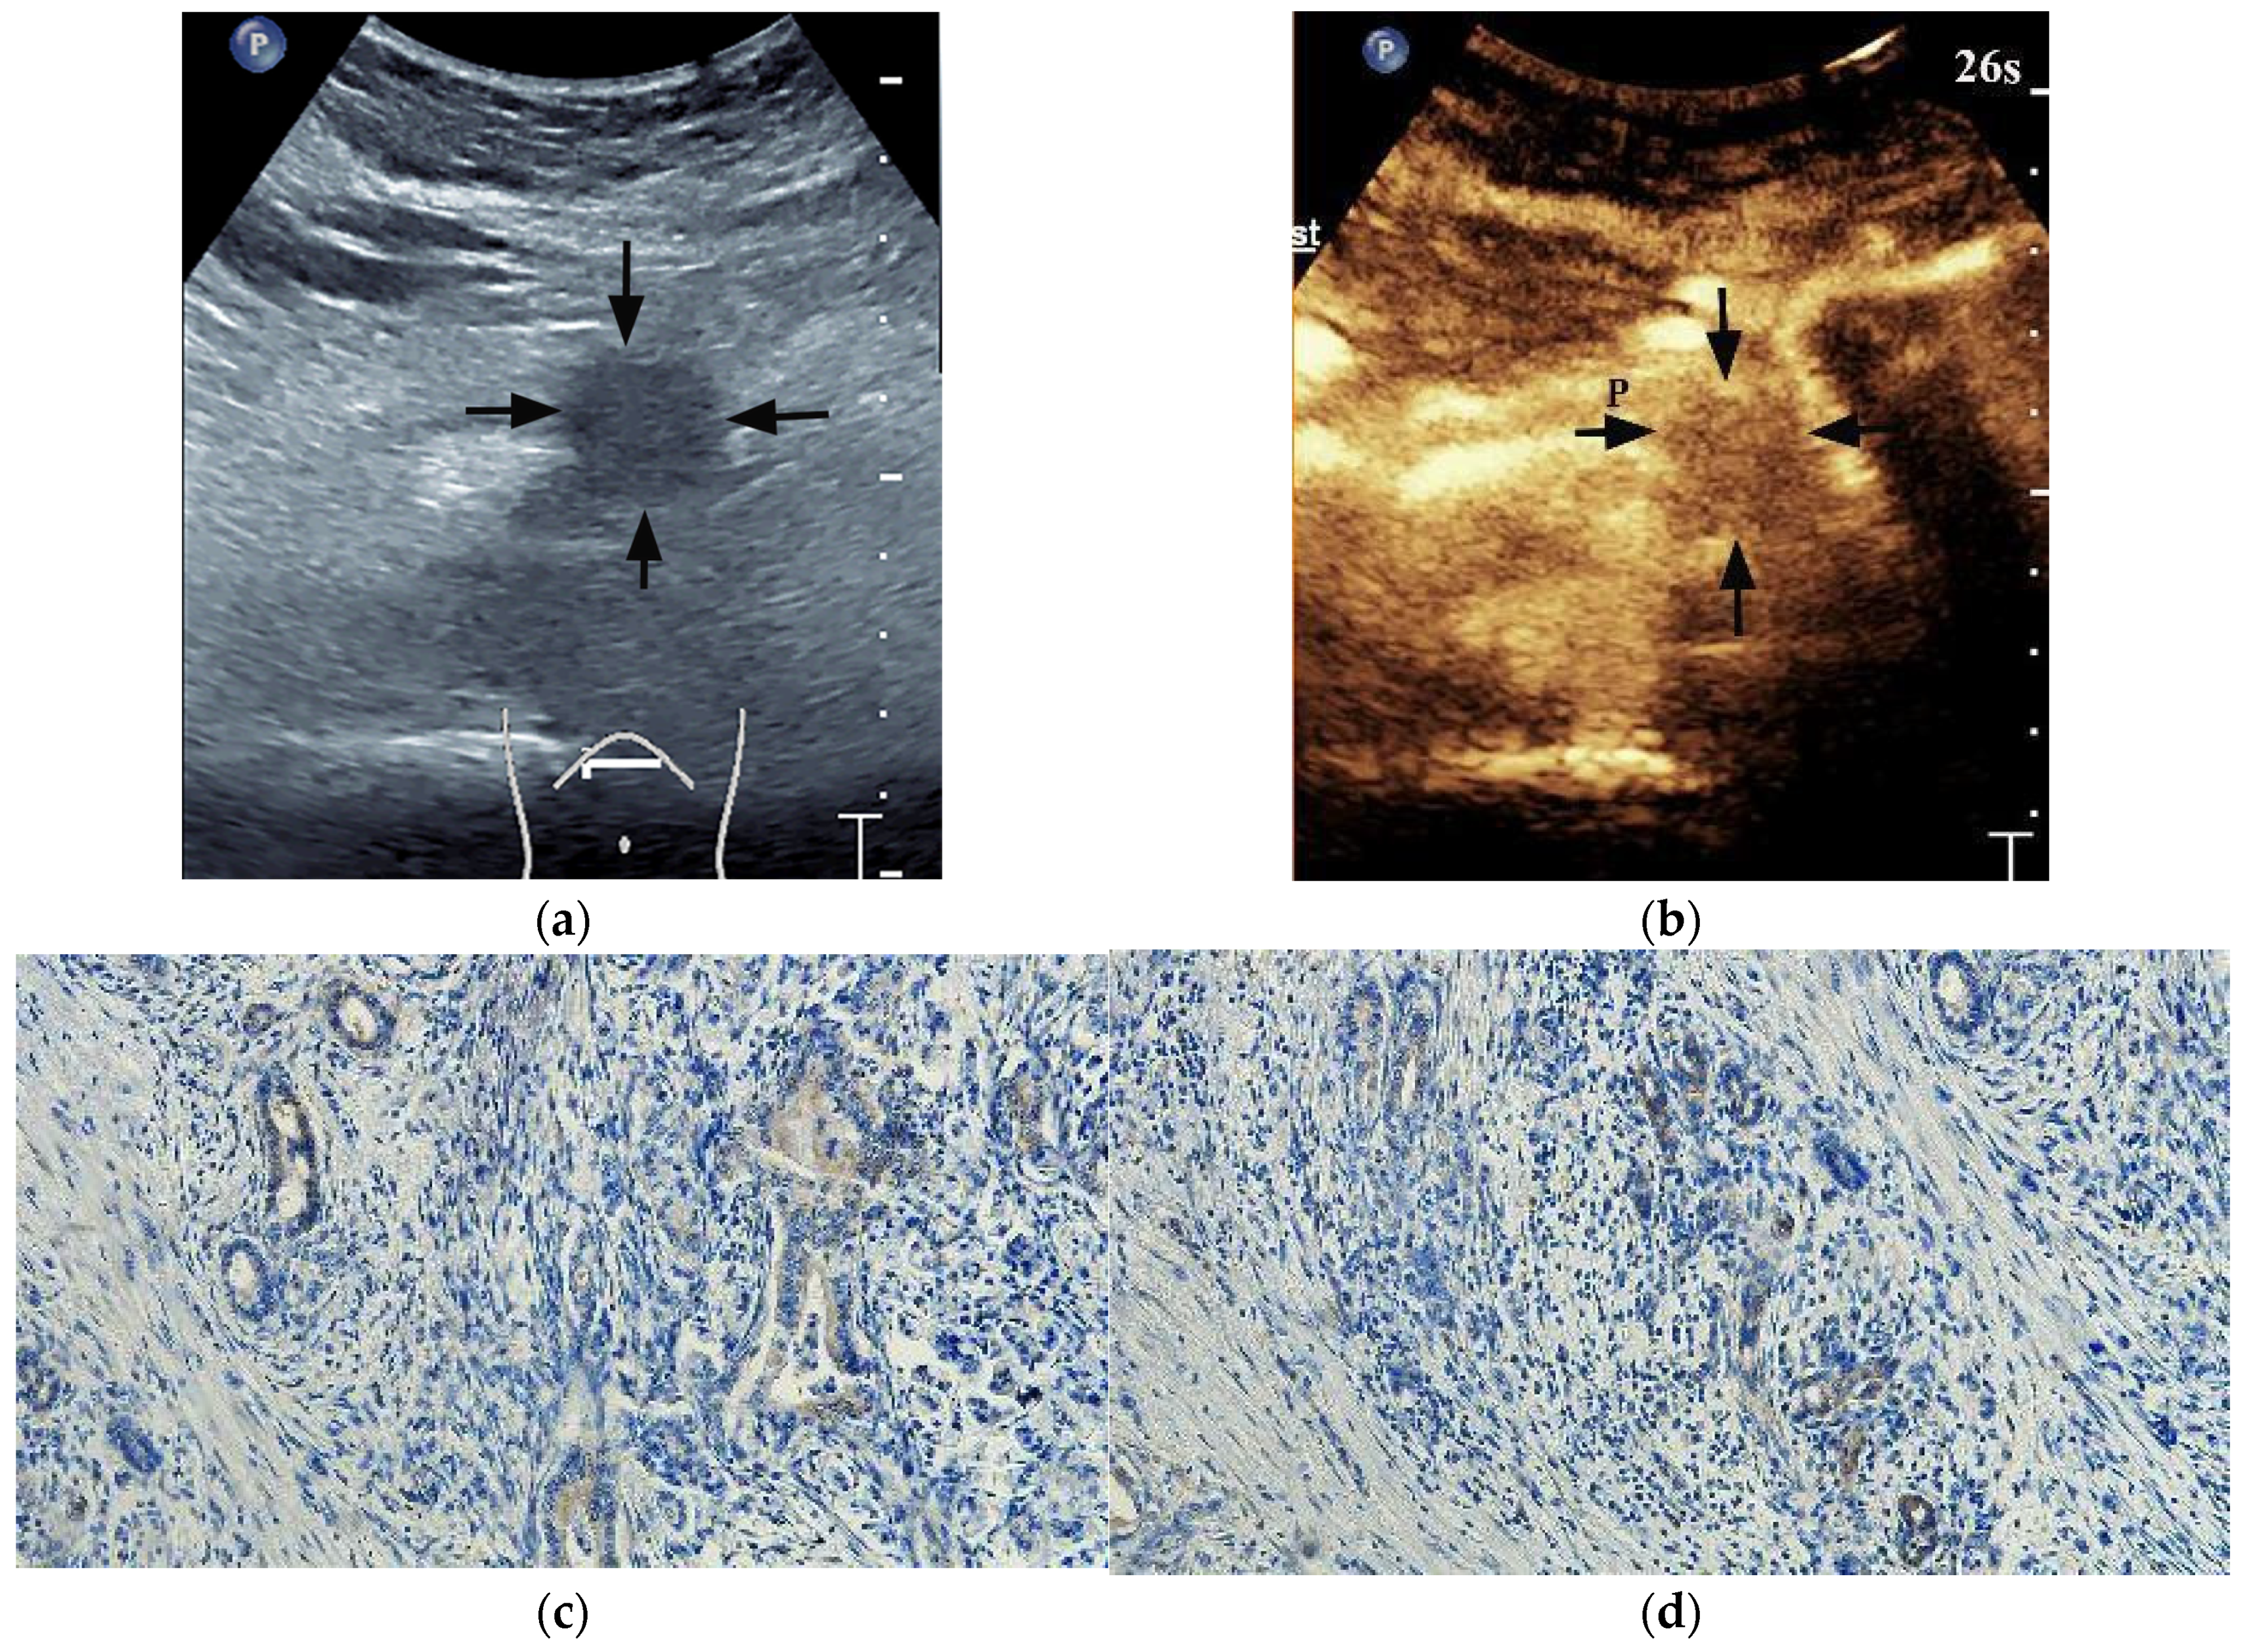

| Completeness of enhancement | ||||||

| Complete enhancement | 35 (68.6%) | 17 (33.3%) | 0.001 | 34 (66.7%) | 18 (35.3%) | 0.003 |

| Incomplete enhancement (enhancement > 50%) | 13 (25.5%) | 22 (43.1%) | 14 (27.5%) | 21 (41.2%) | ||

| Incomplete enhancement (enhancement ≤ 50%) | 3 (5.9%) | 12 (23.5%) | 3 (5.8%) | 12 (23.5%) | ||

| PED | ||||||

| Iso-enhancement | 9 (17.6%) | 19 (37.3%) | 0.027 | 8 (15.7%) | 20 (39.2%) | 0.008 |

| Hypo-enhancement | 42 (82.4%) | 32 (62.7%) | 43 (84.3%) | 31 (60.8%) | ||